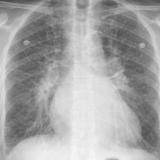

APE 3

Date: 11/05/2005

Views: 3886